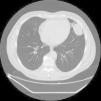

Un paciente varón de 58 años de edad se presentó con dolor en el hemitórax izquierdo que se irradiaba al brazo izquierdo y el hombro. La radiografía de tórax reveló una lesión no definida en el lóbulo superior del pulmón izquierdo. Una tomografía computarizada multicorte mostró un nódulo pulmonar intraparenquimatoso redondeado y localizado periféricamente que medía 53×54mm y se situaba en la parte inferior del lóbulo superior del pulmón izquierdo (língula). La lesión estaba en contacto con el diafragma, el pericardio y la pleura parietal (fig. 1).

En nuestro caso, el estudio de tomografía computarizada multicorte y la inspección intraoperatoria del pulmón mostraron la lesión pulmonar intraparenquimatosa en contacto con el diafragma, el pericardio y la pleura parietal, y simulaba clínicamente una neoplasia maligna. Por lo tanto, la lobectomía se consideró el tratamiento de elección. Aunque son raros, se deben tener en cuenta los lipomas pulmonares intraparenquimatosos en el diagnóstico diferencial de los nódulos pulmonares localizados periféricamente para que se pueda planificar y modificar cuidadosamente el procedimiento quirúrgico.